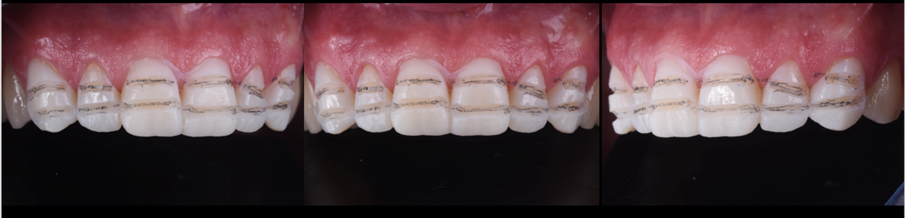

Dostavby byly navrženy v softwaru exocad (obr. 4) a pro jejich výrobu byl zvolen lithium disilikát (obr. 5). Výplně byly adhezivně fixovány v ústech pacienta. Po zvýšení VRO byla incizální okluze pacienta ideální pro rekonstrukci řezákového vedení, pro kterou bylo nutno zajistit pacientovi ortodontickou léčbu (obr. 6). Po ukončení ortodontické léčby byly opotřebené incizální hrany dolních řezáků obnoveny přímou dostavbou kompozitem (obr. 7).

Obr. 6a, b: Situace před a po ortodontickém ošetření.

Obr. 7a-d: Přímá kompozitní náhrada předního sextantu dolní čelisti.